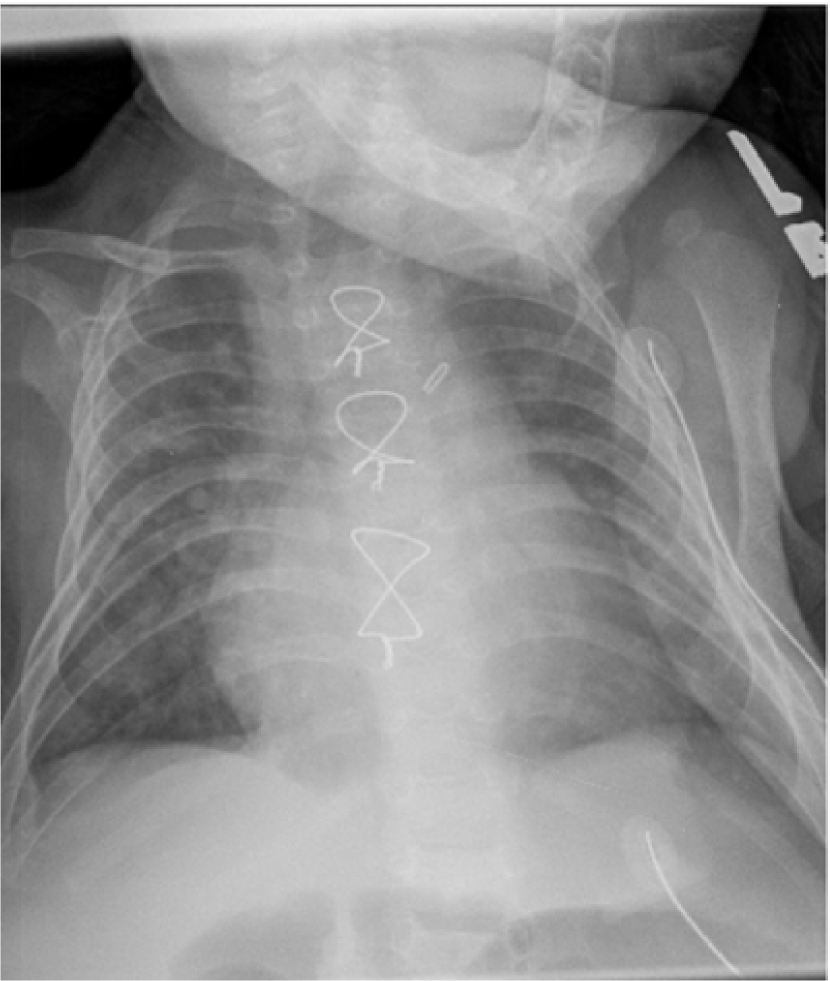

Despite tremendous advancements in tomographic imaging, chest radiography remains the most commonly used imaging modality for pulmonary analysis mainly due to its low cost, low radiation dosage, and widespread availability. Radiation dosage is of particular concern in pediatric applications, especially in neonatal intensive care units where chest radiographs (CXRs) are considered the first option for pulmonary diagnosis [1]. Lung field segmentation is the necessary initial step for image-based pulmonary analysis. Accurate delineation of lung field from CXR, however, is challenging due to ambiguous boundaries, pathologies, occultation of lung field by anatomical structures in thorax, anatomical variation of lung shapes, and size across subjects (Fig. 1). Part of the challenge in developing computer-aided diagnosis (CAD) methods, especially for pediatric cohorts, is also the anatomical shape variation of lung field that occur during growth [2, 3]. As shown in Fig. 1, pediatric cohorts have a more compliant chest wall, small thoracic cage, and relative large abdominal space. Furthermore, the diaphragm of children has smaller apposition area which has a concave shape in the posterior-anterior (PA) view CXR [3]. Therefore, existing approaches to lung field segmentation that are designed primarily for adult cohorts, are not accurate at analyzing the pediatric subjects. Although a few pilot studies such as [2] have been conducted recently to look at the age-related radiological biomarkers in lungs, no comprehensive study of pediatric lung field segmentation exists to the best of our knowledge.

Traditionally, CAD algorithms designed to segment lung field from CXR ignore the retro-cardiac region, i.e., the lung region occluded by heart (Fig. 2(a)). The segmentation label without the retro-cardiac region provides only partial unobstructed lung field. Accurate delineation including the occluded retro-cardiac region, is necessary for correct diagnosis in diseases related to the change in lung capacity such as atelectasis (lung collapse), hyaline membrane disease, transient trochnpea, and Meconium aspirat. Fig. 2(c) presents the correlation between the lung volume estimated from computed tomography (CT) scans and the segmented lung field area from CXR (with and without retro-cardiac region) from 108 individuals. The plot shows a stronger overall correlation between the lung capacity calculated including the retro-cardiac region and the lung volume obtained through CT scans (R=0.80 without retro-cardiac region, R=0.86 including retro-cardiac region; no inspiration/ expiration information was available. R is the correlation coefficient).